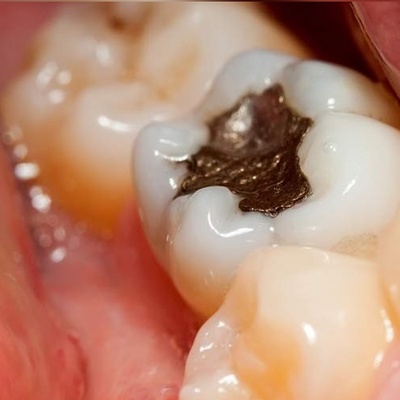

عصب کشی

خدمات بهترین متخصص جراحی لثه چه مواردی را شامل می شود؟

مراقبت های پس از درمان ریشه ی دندان کدامند؟

کشیدن یا عصب کشی دندان شیری ؟ کدام یک بهتر است؟

نکاتی برای جلوگیری از عصب کشی در بارداری

عصب کشی در بارداری امکان پذیر است؟